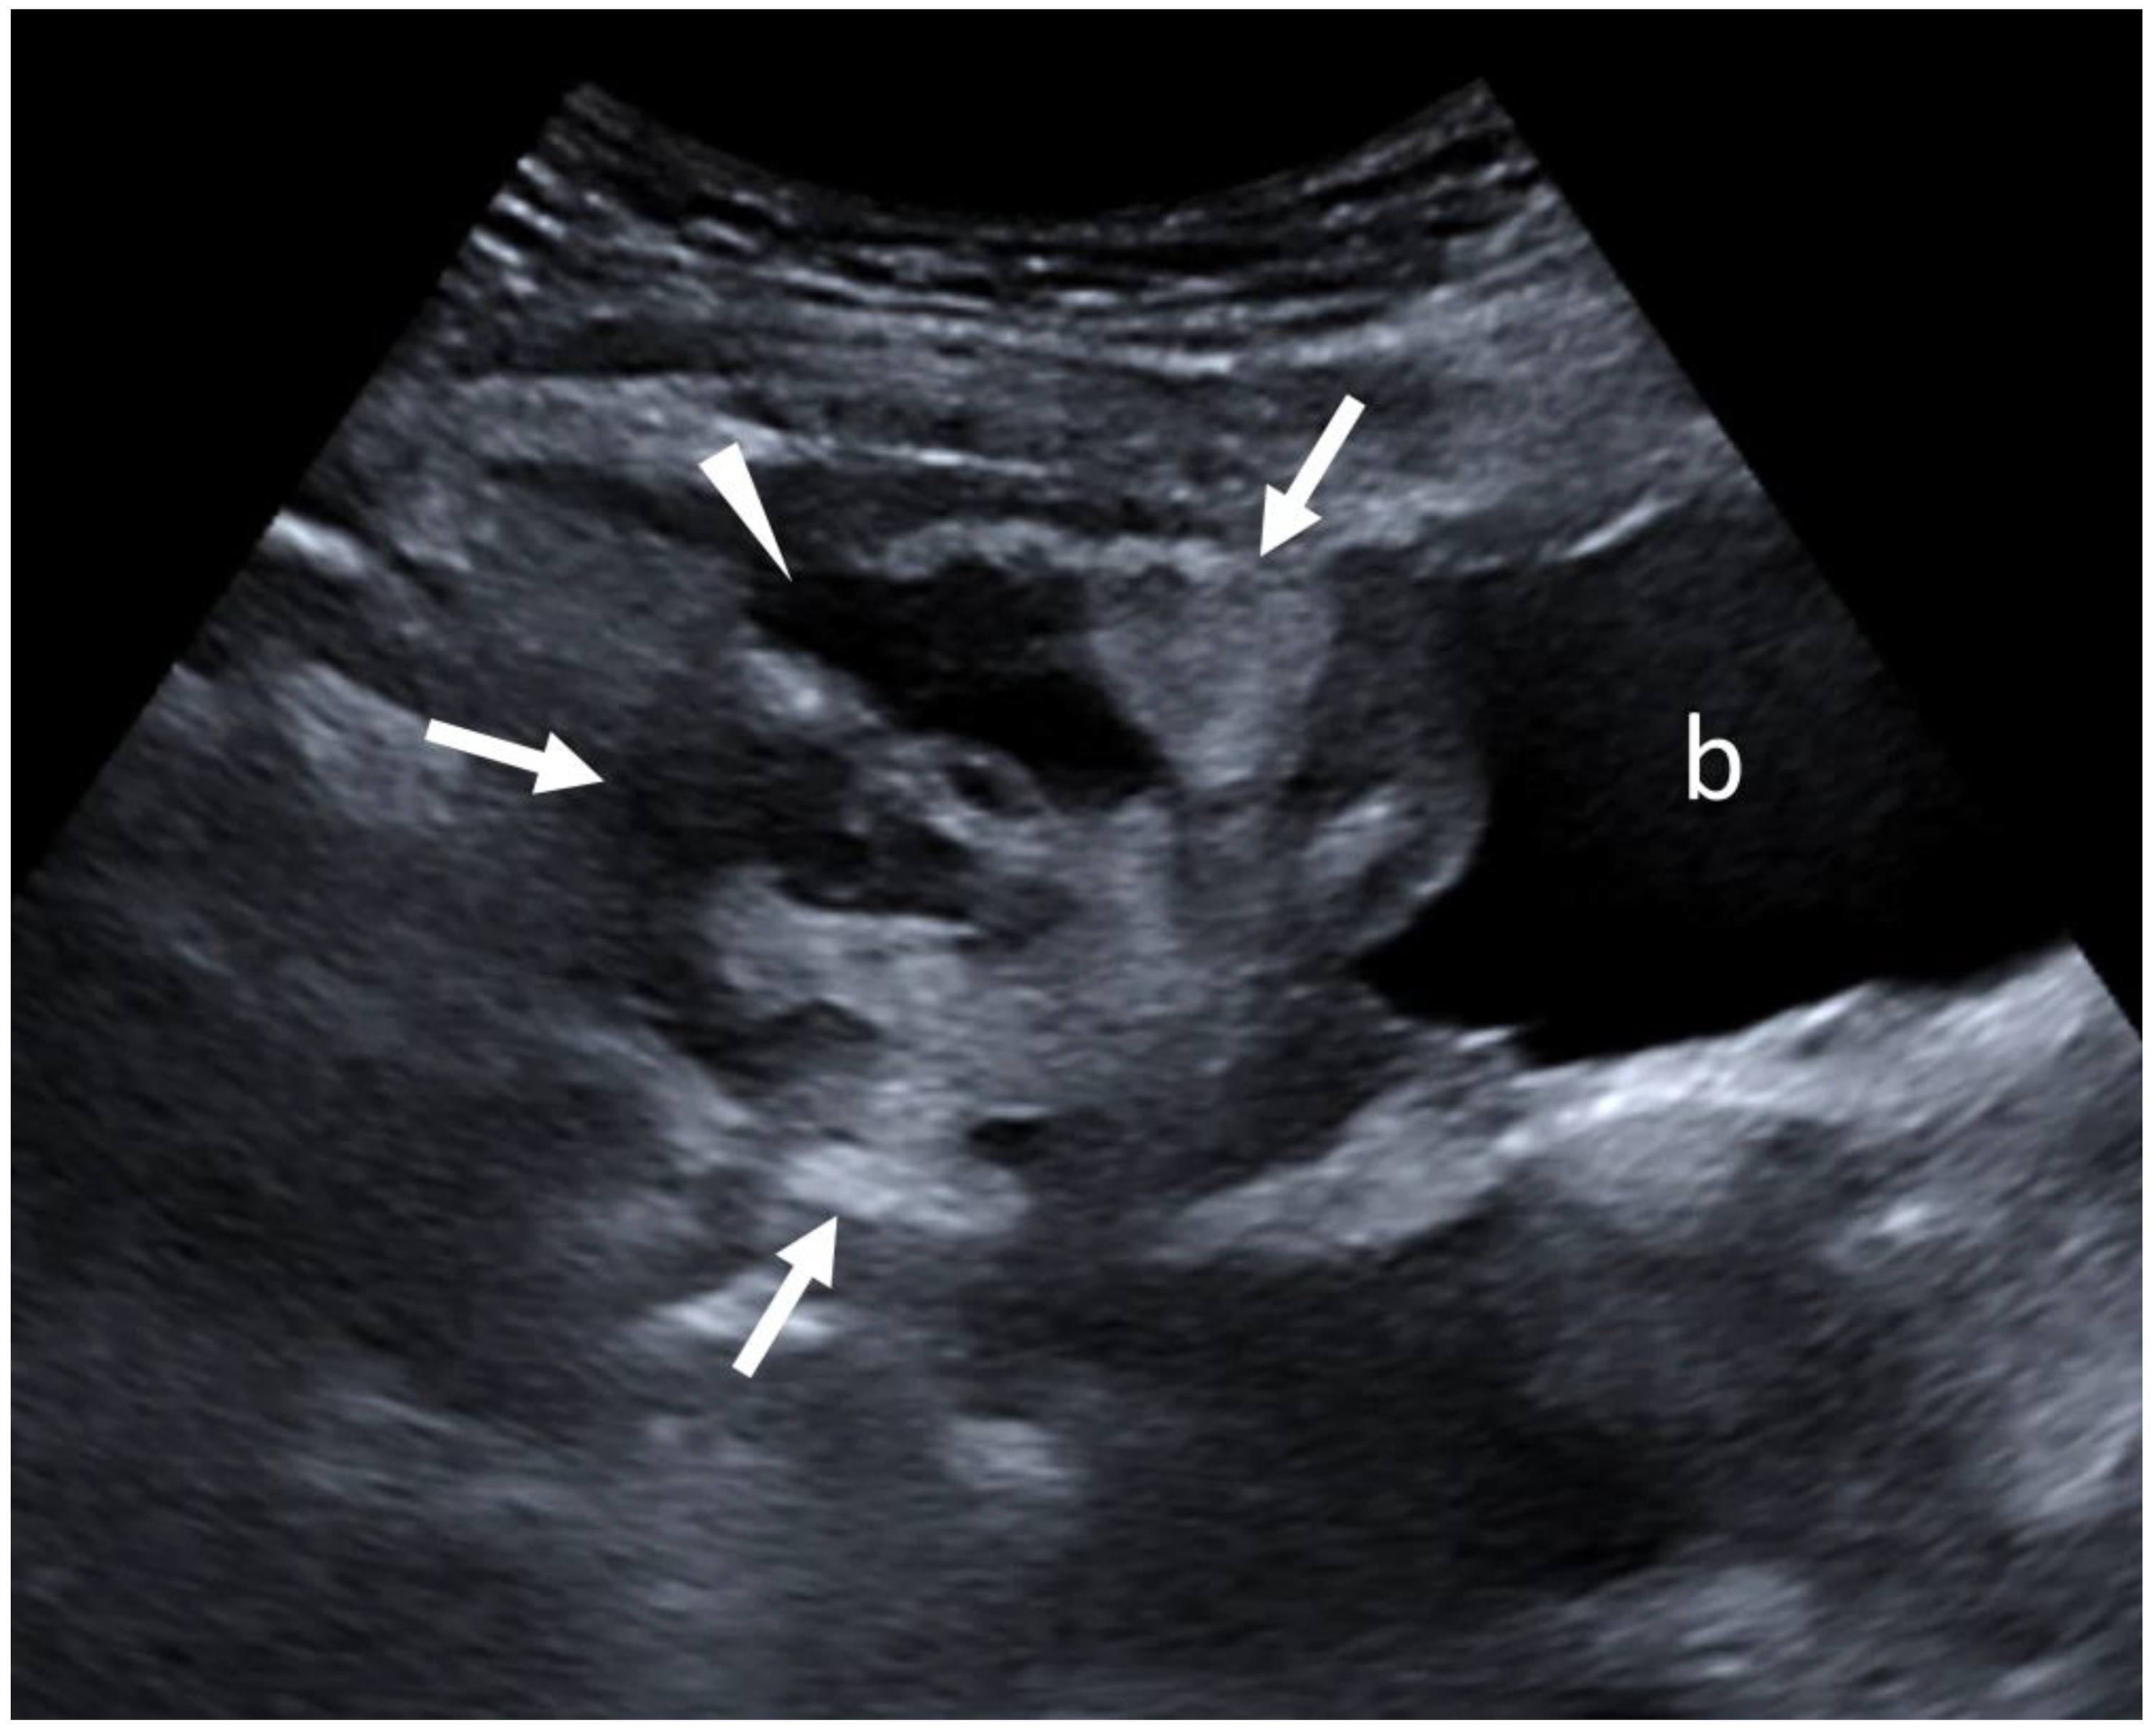

On ultrasound, in a sagittal orientation, the distal part of the greater omentum (white arrows), just above the bladder (b), appeared heterogeneous and was hyperechoic with an anechoic liquid zone corresponding to the abscess in formation (white arrowhead). An ultrasound-guided puncture of the epiploic fluid collection was performed the following day, which confirmed the diagnosis of epiploic abscess with the same bacteria as identified in the endocervical samples. The final diagnosis was therefore that of an epiploic abscess secondary to an upper genital infection with Parvimonas micra. The patient received triple antibiotic therapy (ceftriaxone, doxycycline, and metronidazole) for 15 days and was discharged after 3 days in the hospital and went home. Biological inflammatory syndrome disappeared in three days, and a follow-up ultrasound at one month showed complete regression of the greater omentum fluid collection. Omental abscesses can be primary [1] or, most commonly, secondary to spontaneous or post-operative infarction [2,3]. Omental infarction is usually due to venous insufficiency secondary to trauma, abdominal surgery, or venous thrombosis of the veins of the greater omentum [4,5]. Reactive involvement of the greater omentum has already been described in the context of severe pelvic inflammatory disease with tuboovarian abscess, which acts as an internal barrier to contain the infectious process in the pelvis in case of peritonitis [6]. Although MRI is the most accurate imaging modality for the diagnosis of pelvic abscesses, particularly those secondary to pelvic inflammatory diseases [7], CT and ultrasound are easily accessible modalities that allow for the suspicion of the diagnosis in this clinical case. This observation shows the possible occurrence of a greater omentum abscess secondary to a non-severe pelvic inflammatory disease.